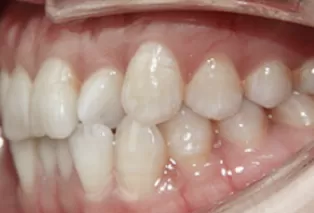

Photos intra-orales